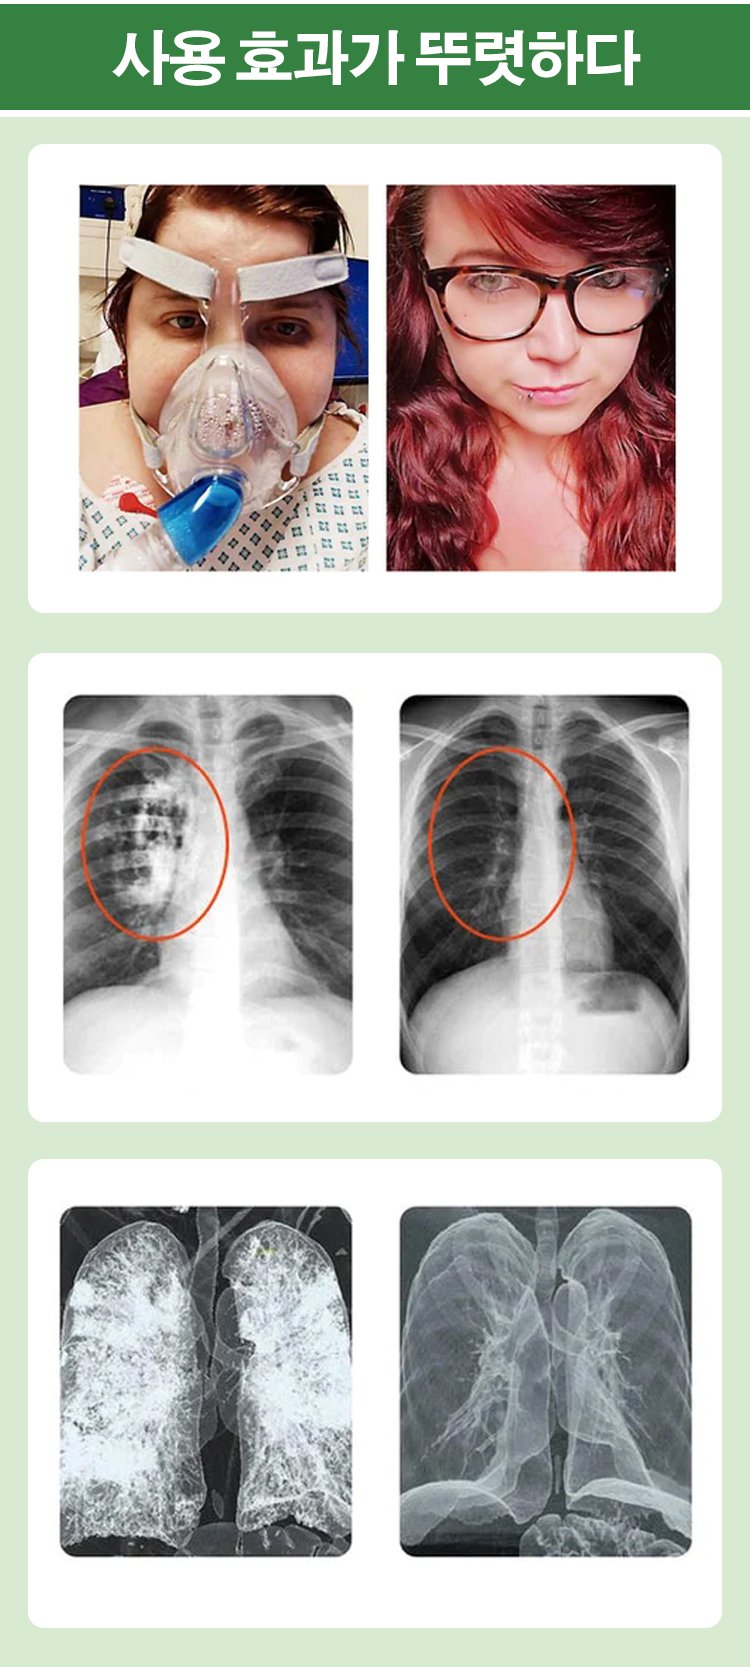

【폐 클리너】목 건강과 폐 정화 해독제

맑은 숨, 건강한 폐! 식물성 함유로 촉촉하게 관리하세요.